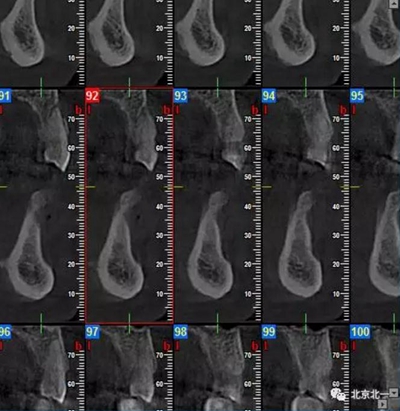

患者術(shù)前片, 最窄骨寬度僅僅3mm,34-35牙位缺失,

CBCT顯示如下圖

如何種植?